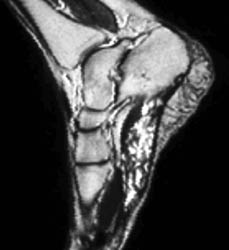

Typically divided into capillary (containing small capillary-like vessels) and cavernous (containing large sinusoids filled with blood) categories. Although lesions are most common in the skin and subcutaneous tissues, they also involve the muscles of the peripheral extremities. They are often irregular and have mixed signal intensity. Usually they are slightly higher in intensity than skeletal muscle on T1 and have markedly high intensity on T2 weighted sequences, with internal septa and slightly lobulated or irregular borders. Numerous serpiginous vessels may be seen.

39 year old male with an extensive soft tissue mass involving the plantar aspect of the foot, dissecting between the third and fourth metatarsals, and extending into dorsum of the foot. The mass has intermediate signal on T1 and very high signal on T2 weighted images, and appears serpiginous.